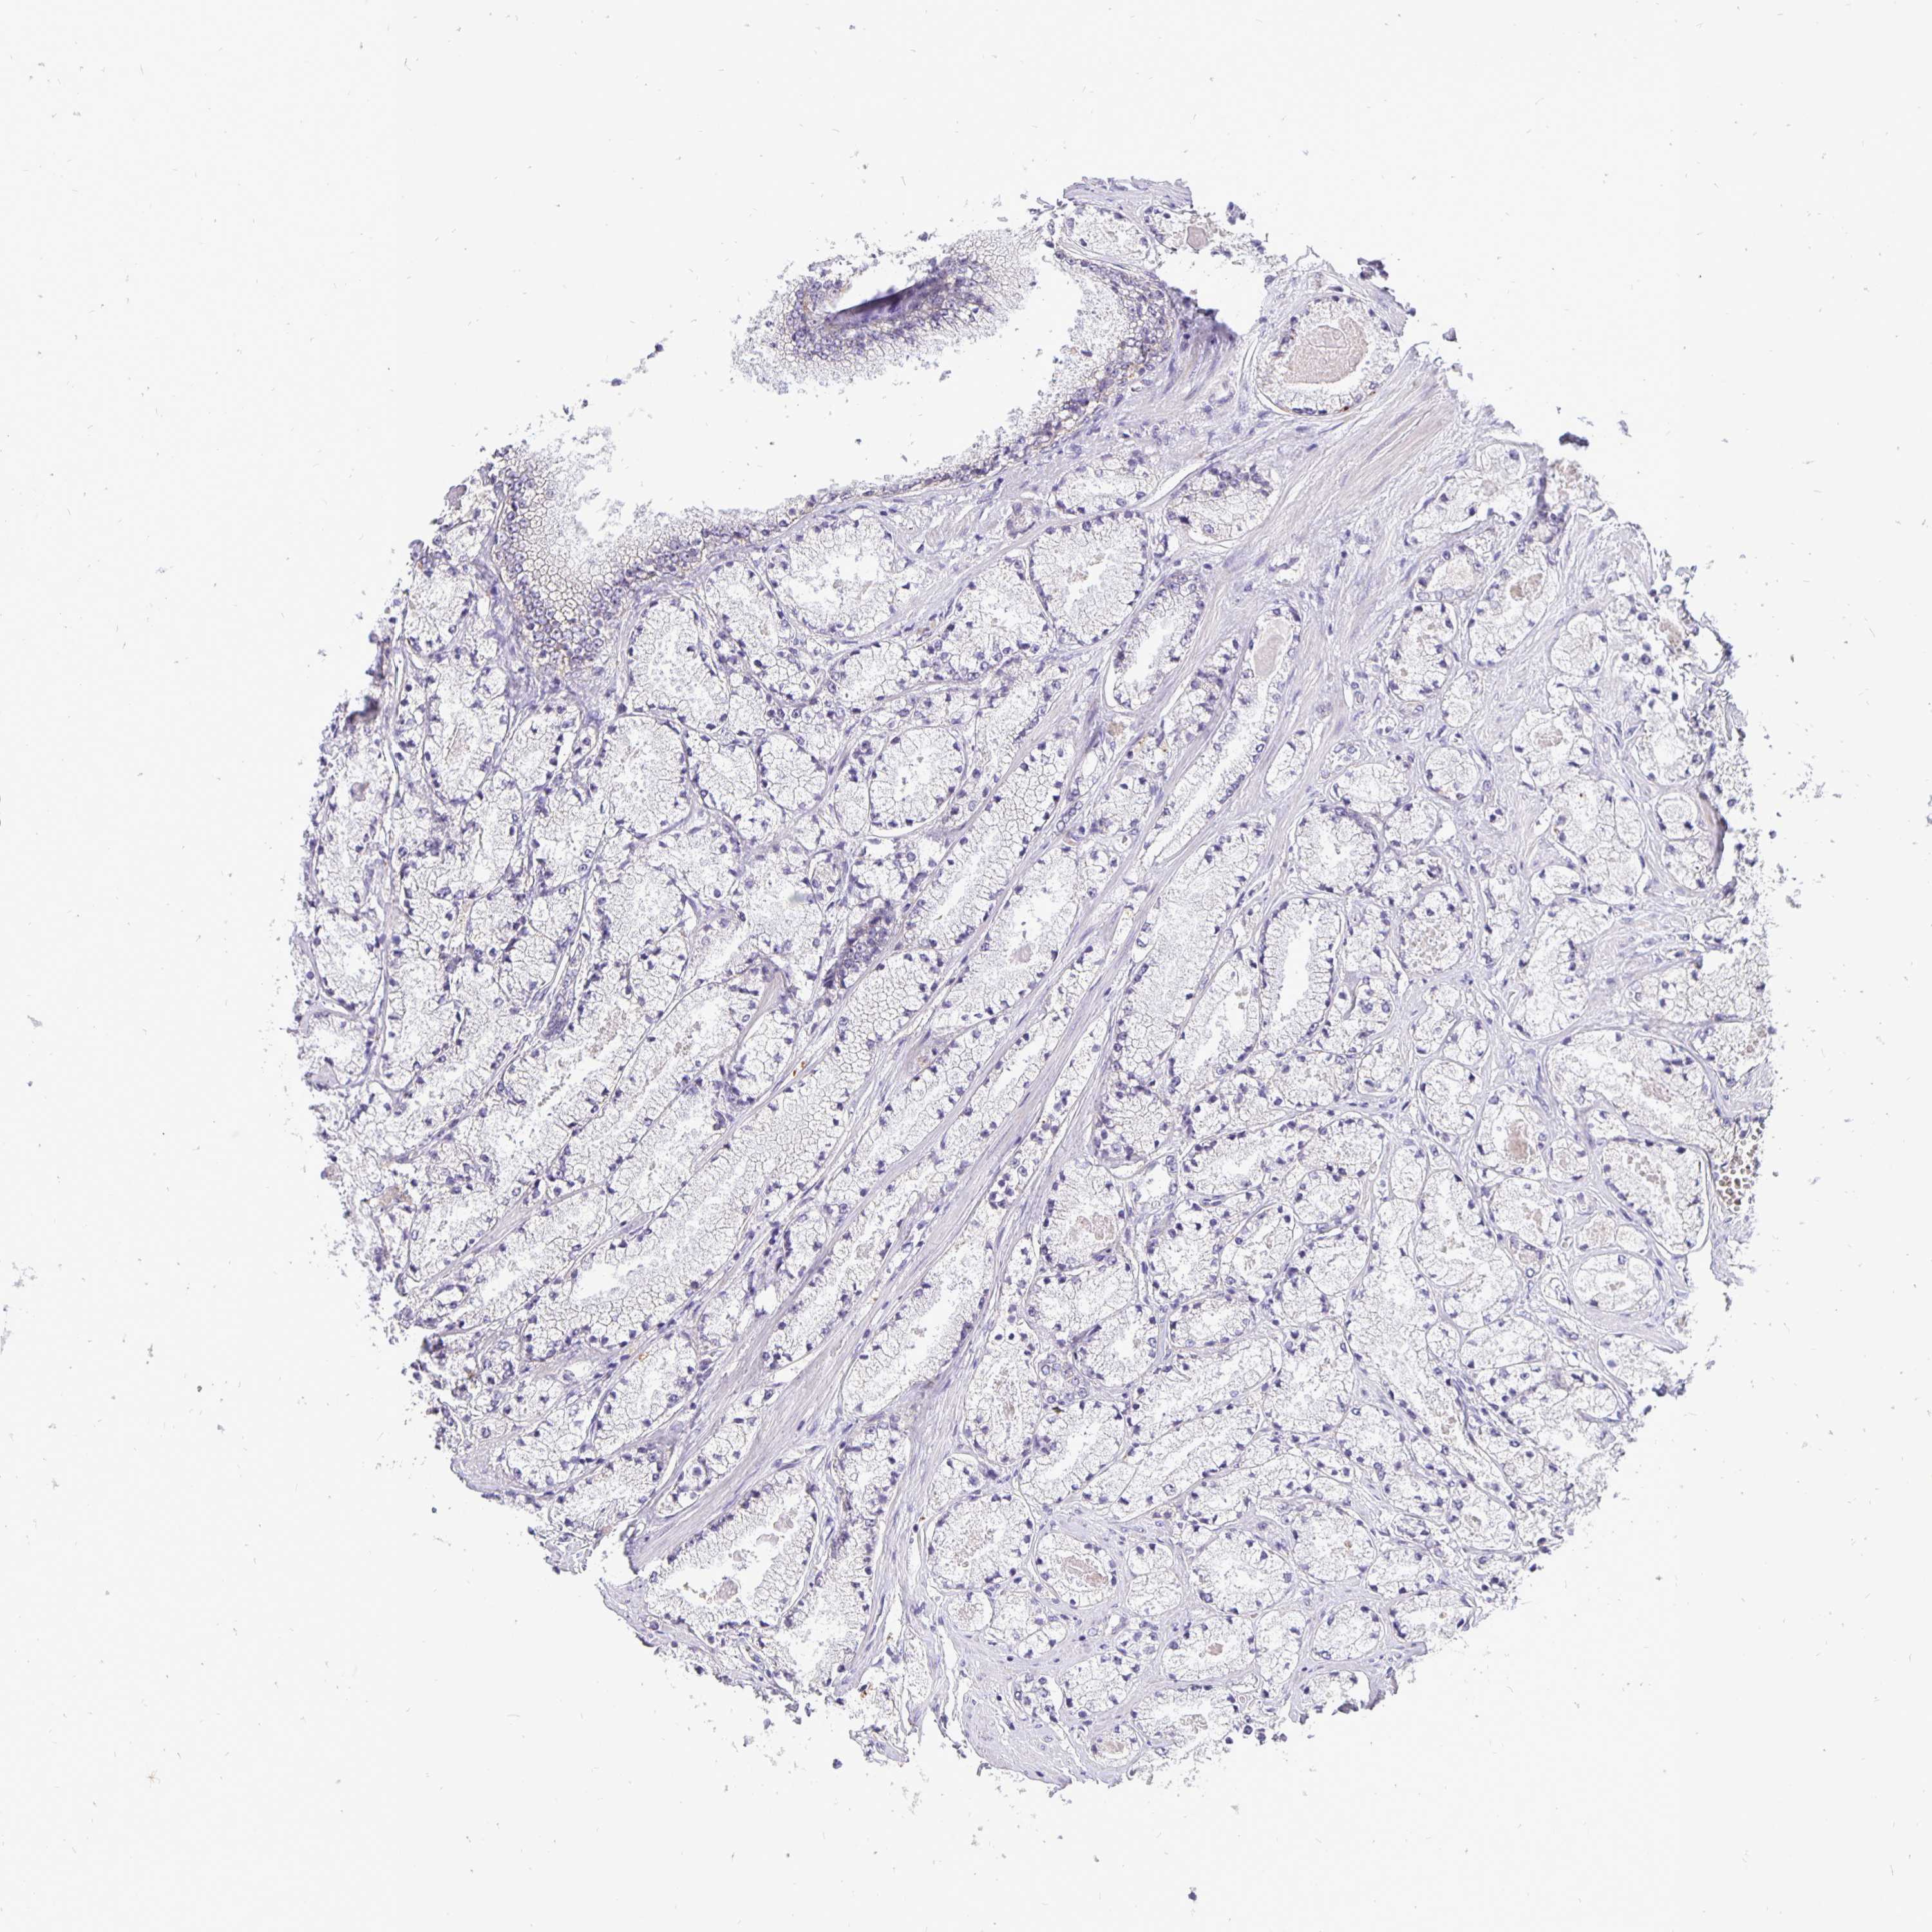

PROSTATE CANCER - Protein expressioni

A mouse-over function shows sample information and annotation data. Click on an image to view it in a full screen mode. Samples can be filtered based on level of antibody staining by selecting one or several of the following categories: high, medium, low and not detected. The assay and annotation is described here.

Antibody stainingi

Antibody staining in the annotated cell types in the current human tissue is reported as not detected, low, medium, or high, based on conventional immunohistochemistry profiling in selected tissues. This score is based on the combination of the staining intensity and fraction of stained cells.

Each image is clickable and will lead to virtual microscopy that enables deeper exploration of all samples and also displays staining intensity scores, fraction scores and subcellular localization as well as patient and tissue information for each sample.

Antibody HPA001383

Antibody CAB000043

Antibody CAB020416

Antibody CAB062555

Adenocarcinoma, Medium grade

Adenocarcinoma, Low grade

Adenocarcinoma, High grade

Adenocarcinoma, NOS